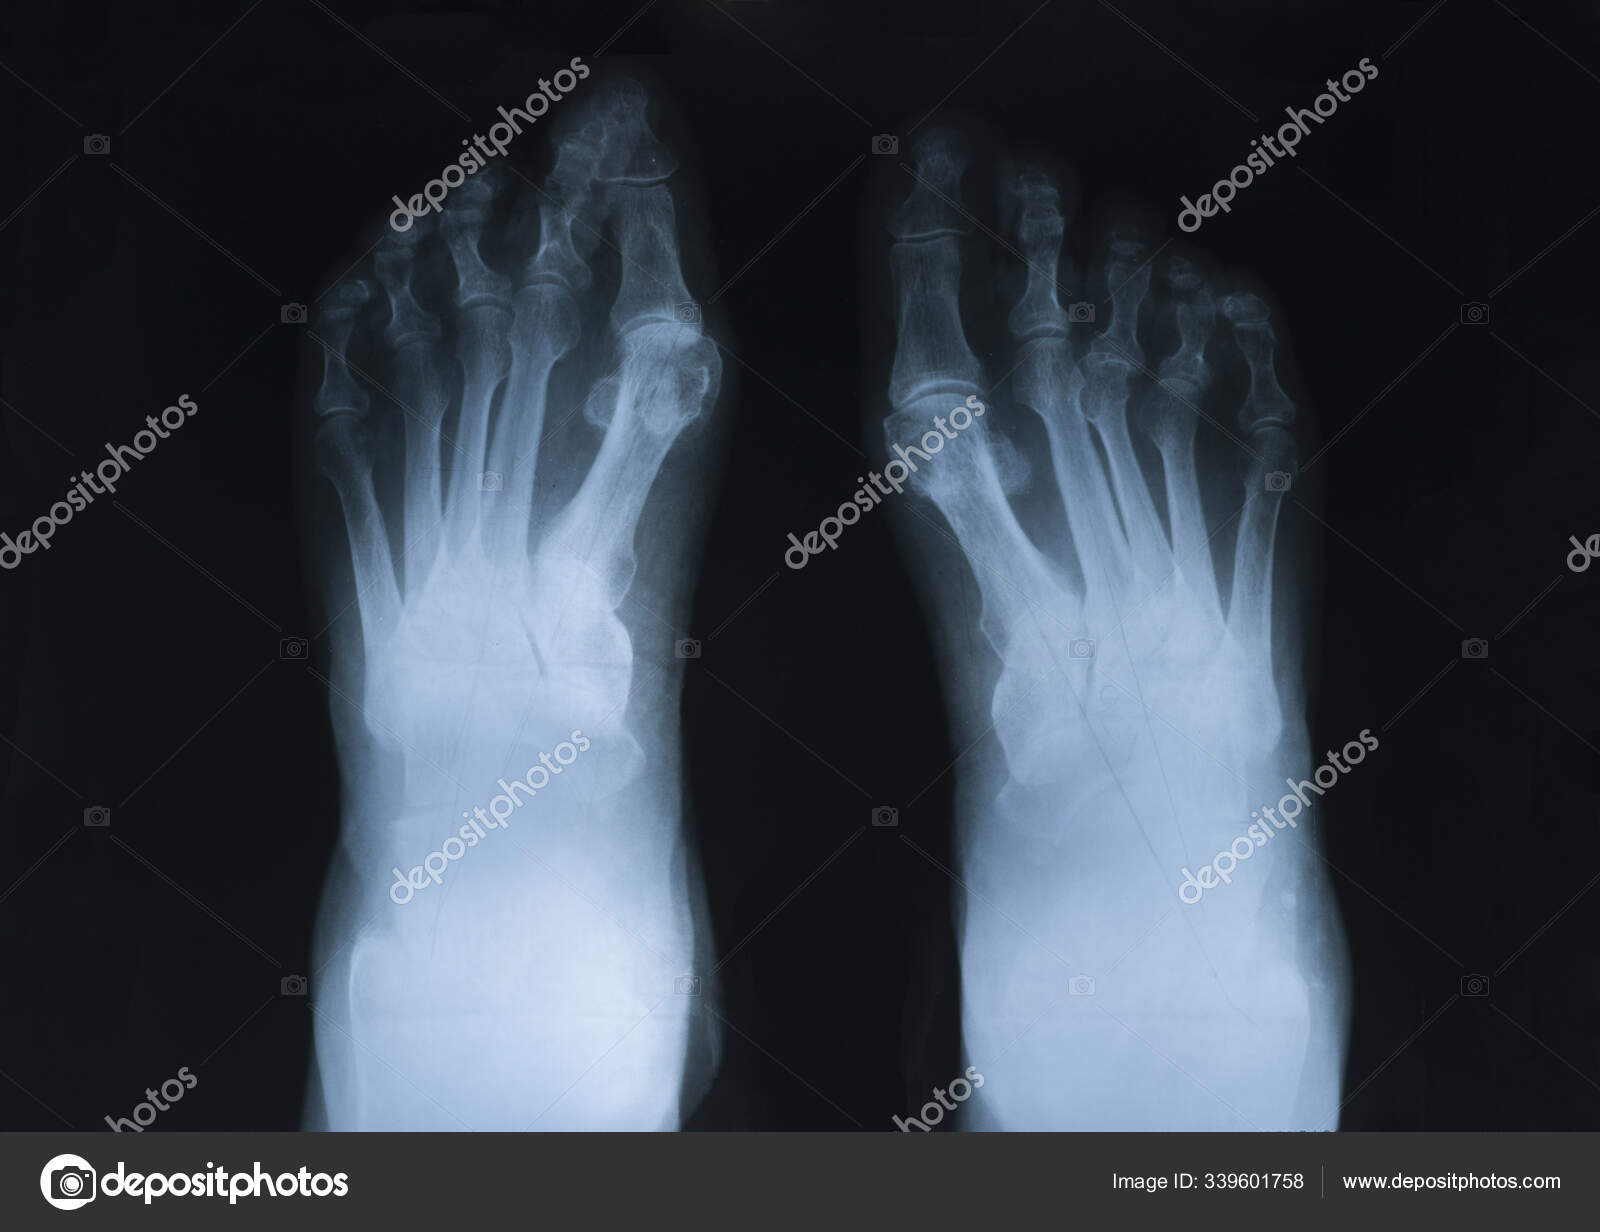

The rheumatoid community on reddit. For more information and past images of the month, go to. These tests primarily look for bone damage in the patient's joints caused by the inflammation associated with ra. The 2010 rheumatoid arthritis classification criteria help doctors diagnose rheumatoid arthritis. It is caused when the immune system (the body's defense system) is not working properly. The earliest manifestation of rheumatoid arthritis of the forefoot is synovitis of the mtp joints with eventual hyperextension deformity of the mtp joints including distal. Sorptiometry should be performed to diagnose. It typically results in warm, swollen, and painful joints.

The rheumatoid community on reddit. The earliest manifestation of rheumatoid arthritis of the forefoot is synovitis of the mtp joints with eventual hyperextension deformity of the mtp joints including distal. Rheumatoid arthritis (ra) imaging tests are used to look for signs of ra and to monitor the disease's progression. (uk) national rheumatoid arthritis society helpline. </b>small joints of the feet, wrists, and hands are frequently involved by a reduction of osteoporosis; Rheumatoid arthritis (ra) is a chronic autoimmune multisystemic inflammatory disease that affects many organs but predominantly attacks the synovial tissues and joints. Rheumatoid arthritis (ra) is the most common type of autoimmune arthritis. Rheumatoid arthritis is considered an indication for resurfacing of the patella during total knee arthroplasty.

If the pattern of disease is not symmetrical, then a different diagnosis should be considered. In rheumatoid arthritis, the body's immune system attacks its own healthy cells inside certain joints, leading to an inflammatory response. For more information and past images of the month, go to. However, they are not useful in the early stages of rheumatoid arthritis, before joint damage occurs. </b>rheumatoid arthritis (ra) is a polyarticular disease with bilateral and symmetric distribution. Sorptiometry should be performed to diagnose. The rheumatoid community on reddit. Rheumatoid arthritis (present for >10 years). The ulnar styloid is destroyed with the rest of the distal ulna (white arrow), there is destruction of the carpal bones (yellow arrow) and there is dislocation of the 1st metacarpal on the destroyed trapezium. Rheumatoid arthritis affects around 400,000 adults aged 16 and over in the uk. Reddit gives you the best of the internet in one place. Ra causes pain, swelling, stiffness, and loss of function in joints. The earliest manifestation of rheumatoid arthritis of the forefoot is synovitis of the mtp joints with eventual hyperextension deformity of the mtp joints including distal.